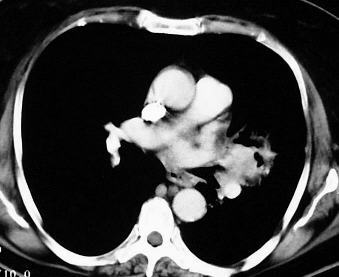

Lymphome

Mediastinale Lymphknotenvergrösserungen kommen bei Hodgkin-Lymphomen in mehr als 50% und bei Non-Hodgkin-Lymphomen in ca. 20% der Fälle vor. Die Lymphome sind computertomographisch als noduläre oder unstrukturierte weichteildichte Raumforderungen gekennzeichnet, die paratracheal, paravertebral, retrokrural, perikaval, präaortal und retrosternal gelegen sind.

Eine wichtige Differentialdiagnose ist die bihiläre Lymphadenopathie bei Sarkoidose: